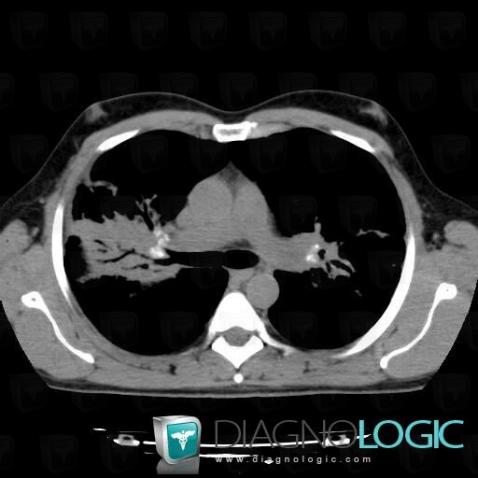

Sarcoïdose, Parenchyme pulmonaire, Scanner

Voici les informations spécifiques à l'image clé ci dessus:

- Diagnostic Sarcoïdose, Localisation(s) Parenchyme pulmonaire, comportant les gammes Maladie prédominant en péri hilaire, Condensation alvéolaire localisée, Condensation alvéolaire chronique